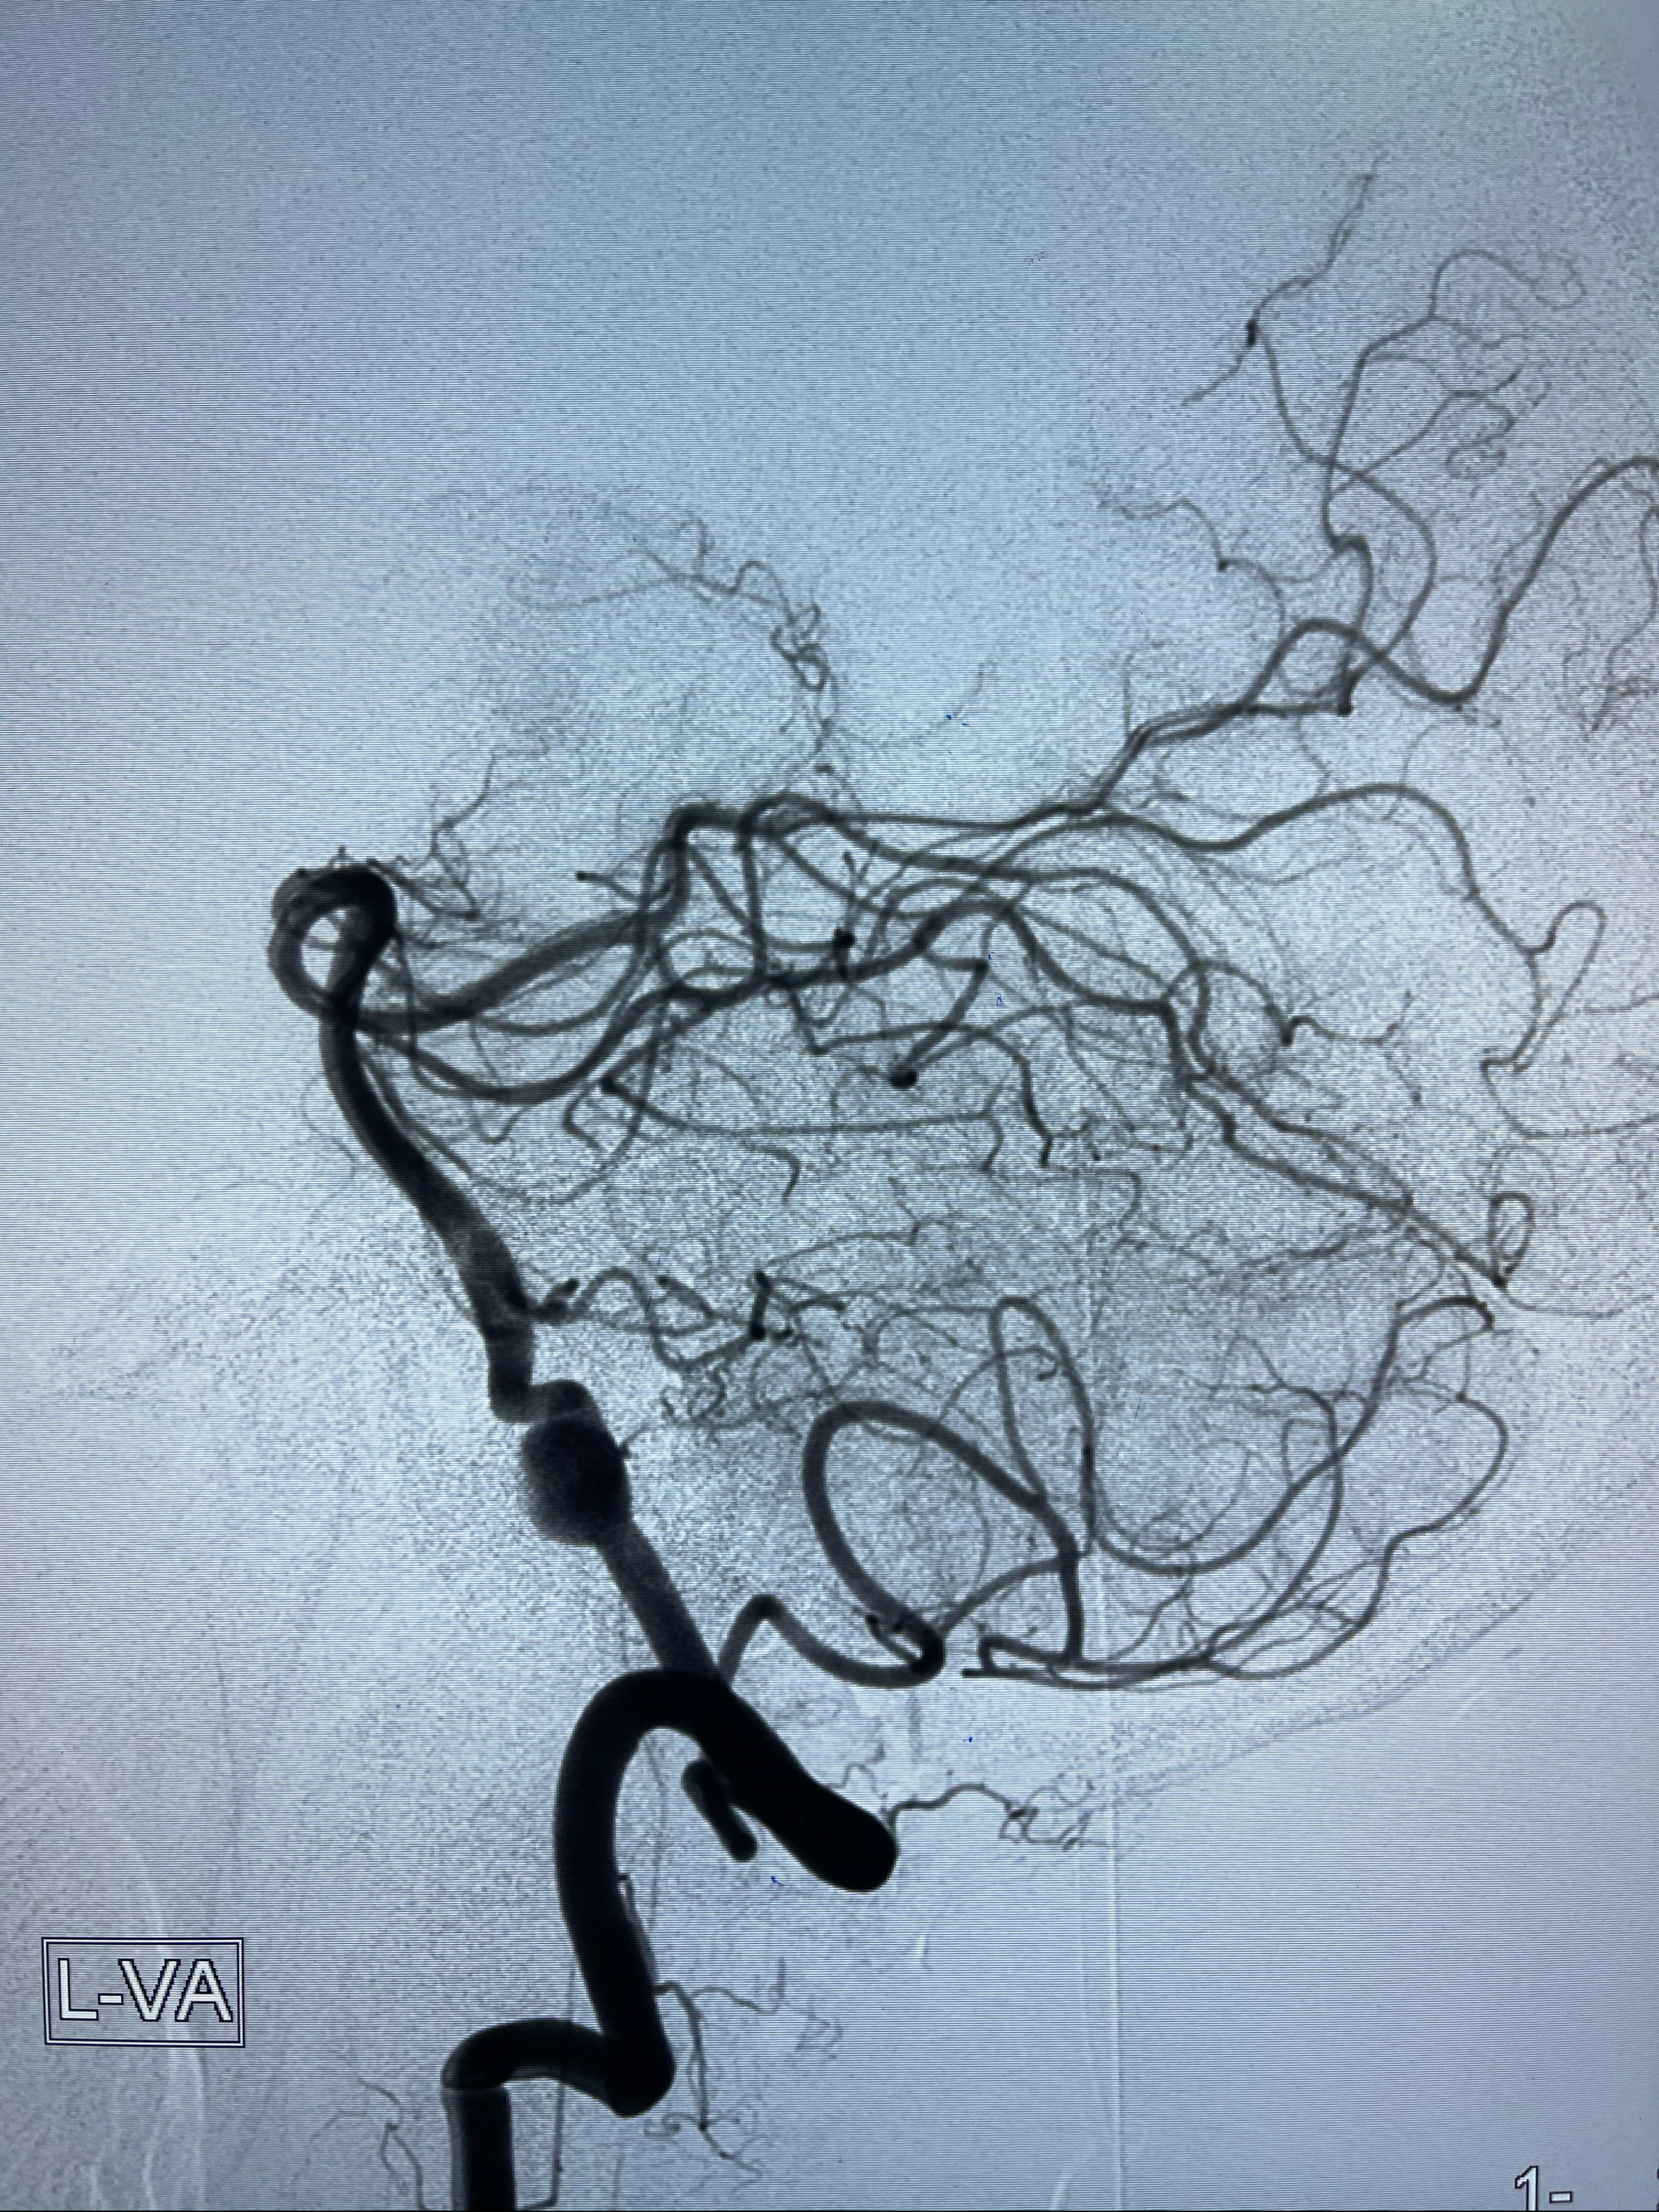

即刻造影

左侧椎动脉V4夹层动脉瘤多支架辅助栓塞:

1.Enterprise4.0-23mm;

2.Tubridge3.5-30mm密网支架